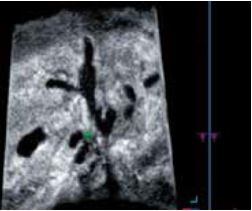

Холангіокарцинома

При оцінці ступеня інфільтрації холангіокарциноми на 3D-реконструкціях неможливо візуалізувати суцільність жовчної протоки на одному зображенні в С-площині (рис.5б). Однак, простеживши додаткові точки в просвіті і відобразивши їх за допомогою Curved MPR, можна сформувати вигнуту С-площину. У вигнутій С-площині (рис.5в) можна чітко візуалізувати безперервність жовчної протоки, що дозволяє легко оцінити ураження та прилеглі ділянки. Крім того, Shadow Glass (Рис. 5г) дозволяє відобразити задню стінку, що дає змогу чіткіше спостерігати за всією структурою жовчної протоки.

а) А-площина

б) Звичайна С-площина

в) Вигнута С-площина (OmniView)

г) Shadow Glass

Рисунок 5. Діагностика холангіокарциноми за допомогою Smart Sensor 3D